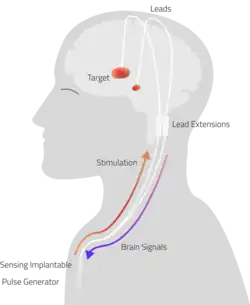

Deep brain stimulation (DBS) is a type of neurostimulation therapy in which an implantable pulse generator is surgically implanted below the skin of the chest and connected by leads to the brain to deliver controlled electrical impulses. These charges therapeutically disrupt and promote dysfunctional nervous system circuits bidirectionally in both ante- and retrograde directions.[1] Though first developed for Parkinsonian tremor, the technology has since been adapted to a wide variety of chronic neurologic disorders.[2]

The DBS system consists of three components: a neurostimulator known as an implanted pulse generator (IPG), its leads and an extension. The neurostimulator has titanium housing and a battery that sends electrical pulses to the brain to interfere with neural activity through deafferentation.

The leads are two coiled wires insulated in polyurethane with four platinum-iridium electrodes that allow delivery of electric charge from the battery pack implanted in the chest wall. The battery is usually situated subcutaneously below the clavicle and rarely in the abdomen. The leads, in turn, are connected to the battery by an insulated extension wire which travels from the chest wall superiorly along the back of the neck below the skin, behind the ear, and finally enters the skull through a surgically made burr hole to terminate in the deep nuclei of the brain.[20] Microelectrodes (usually 1–5) are delivered through the burr holes. A combination of microelectrode recordings, microstimulation, macrostimulation, and neurophysiological mapping at the level of single neurons or local neuronal populations through local field potential analyses are used to increase specificity of placement for the most precise neurophysiologic effect possible.[2]